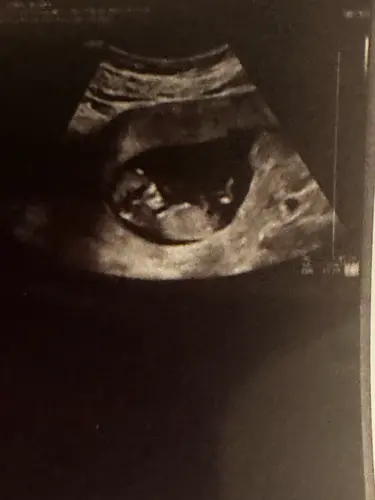

12 weken echo wat denken jullie 😍

Ik denk een jongen😍